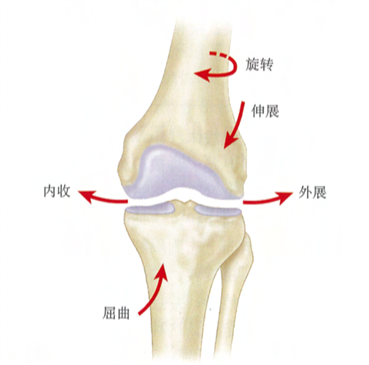

人体的膝关节内部构造什么样?

人类膝关节的解剖结构比较复杂,由股骨、胫骨、髌骨及围绕在它们周围的肌肉、韧带、软组织构成,膝关节一共分为三个间室,即内侧间室、外侧间室和髌股间室,围绕着三个间室有着三个重要的运动轴线,即胫股关节屈曲轴、髌股关节运动轴、膝关节旋转轴,这些运动的稳定主要依靠膝关节周围韧带参与,其中比较重要的有3组:

内外侧间室的中间有两条韧带,即前交叉韧带(ACL)和后交叉韧带(PCL),它们是膝关节屈伸及旋转活动时的重要稳定结构;

内侧间室的内侧和外侧间室的外侧也各有一条韧带,即内侧副韧带(MCL)和外侧副韧带(LCL),它们是膝关节旋转和内外翻活动时的重要稳定结构。

前方的髌骨由上方的股四头肌和下方的髌韧带固定,在股骨滑车上活动,是膝关节屈伸活动时的重要稳定结构。

人类膝关节内部构造和“三个间室”

在正常步态周期中,膝关节运动发生在3个独立平面上,称作“三轴运动”